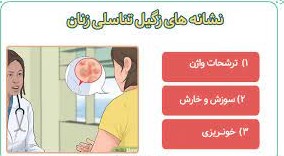

علائم زگیل تناسلی در زنان

این ویروس باعث ایجاد زگیل تناسلی و سرطان در زنان شده و یا گاهی اوقات بدون علائم است. از علائم و نشانه های زگیل تناسلی در زنان می توانیم به خارش، سوزش، یا حساسیت در اطراف واژن اشاره کنیم. از علائم و نشانه های دیگر زگیل های تناسلی در زنان می توانیم به این موارد اشاره کنیم:

- ممکن است زگیل ظاهری شبیه به گل کلم داشته باشد.

- ایجاد خارش، درد و سوزش در ناحیه تناسلی از علائم این بیماری است.

- زنانی که دچار زگیل تناسلی در داخل واژن می شوند، ممکن است علائمی از قبیل خونریزی پس از رابطه جنسی یا علائم غیر طبیعی واژن داشته باشند. همچنین اگر زگیل در مجاری ادرار ایجاد شود، ممکن است موجب انسداد مجاری ادرار شود.